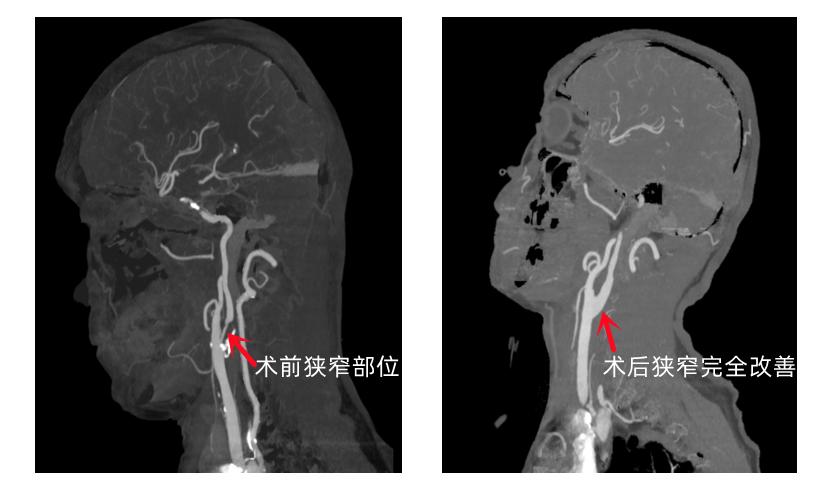

该患者为男性,67岁,发现右侧颈内动脉狭窄已一年多,近一个月反复头晕摔倒,他打听到我院神经外科是省级临床重点专科,于是慕名前来。在神经外科门诊,学科带头人、院长黄纯海为该患者做了细致检查,发现其颈部血管CTA提示:右侧颈内动脉起始部重度狭窄,B超提示:狭窄程度70-90%,随时可能出现斑块脱落导致急性大面积脑梗死危及生命,马上将患者收治入院。

神经外二科手术团队积极完善术前准备,在上级专家的指导及麻醉医生的保驾护航下,该团队顺利为患者施行了右侧颈动脉内膜剥脱术。术中探查发现,患者颈动脉近乎闭塞,其内充填大量钙化硬质斑块,显微镜下顺利为患者清除掉增厚的颈动脉内膜和粥样硬化斑块,恢复了颈动脉血流。术后经过ICU的密切监护和神经外二科医护团队的精心治疗、护理,患者平稳度过围手术期,无术后高灌注综合征、脑卒中等并发症,7天后痊愈出院。